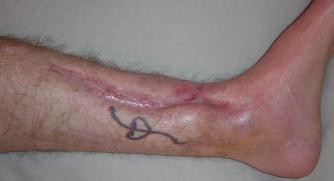

Postoperative (12th) images of left ankle

The images displayed here were created at various appointments following surgery performed by Dr. Daniel Saunders. In the X-Ray you can see

where Dr. Saunders has removed the fibula plate, joined the tibia and fibula with a screw, built-up the area of the tibia where previously

there was considerable absence of bone and lastly added the EBI OsteoGen-M Bone Stimulator (dual lead). The photos show the left side site

where the fibula plate was removed, the top site where donor bone, bone filler material and the stimulator were added and the right side

where the tissue has burst because of swelling. Liam was placed on an IV drip of Vancomycin following surgery to combat the potential onset

of Osteomyelitis. The image of the cast includes the fibula plate that was removed during surgery. The next images were taken later and show

that the staples and stitches were removed. In one of the images, you can see Liam's wife Madeline helping with leg cleanup and in one image

can be seen the EBI representative after being put to work (holding up the left leg while the latest cast cures) by Dr. Saunders. Later shots show

a healing tissue burst site with some overgrowth and Dr. Saunders cauterizing the overgrowth. Bones shifting too much (shown in X-Rays). The

last images are of the left ankle prior to the 13th surgery.